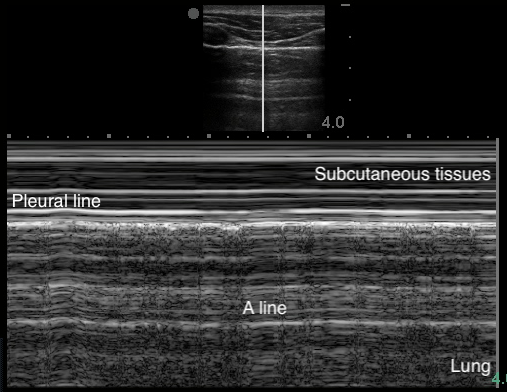

- Figure 4. A-lines

Video 1. A-lines - Occur from the emitted US wave reflecting back and forth between the transducer and the pleural line

- The distance from transducer to pleural line is the same as between the equidistant intervals separating each subsequent A-line.

- The artifacts’ brightness decreases with depth as energy is lost through repeated reflections.